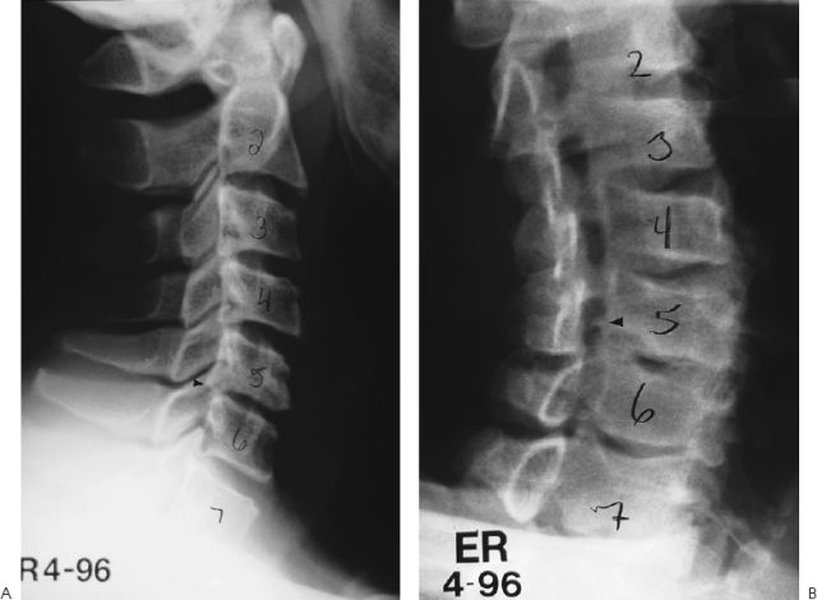

• X-rays (Projectional Radiography): Often an initial study, X-rays can show bone spurs, narrowing of disc spaces, fractures, or spinal alignment issues.

• Magnetic Resonance Imaging (MRI): MRI provides detailed images of soft tissues, including discs, nerves, and ligaments. It is excellent for identifying herniated discs, spinal stenosis, and tumors. It's important to correlate MRI findings with clinical symptoms, as disc herniations can be present in asymptomatic individuals.

• Computed Tomography (CT) Scan: CT scans provide more detailed images of bony structures than X-rays and can be useful for identifying bone spurs or foraminal stenosis.